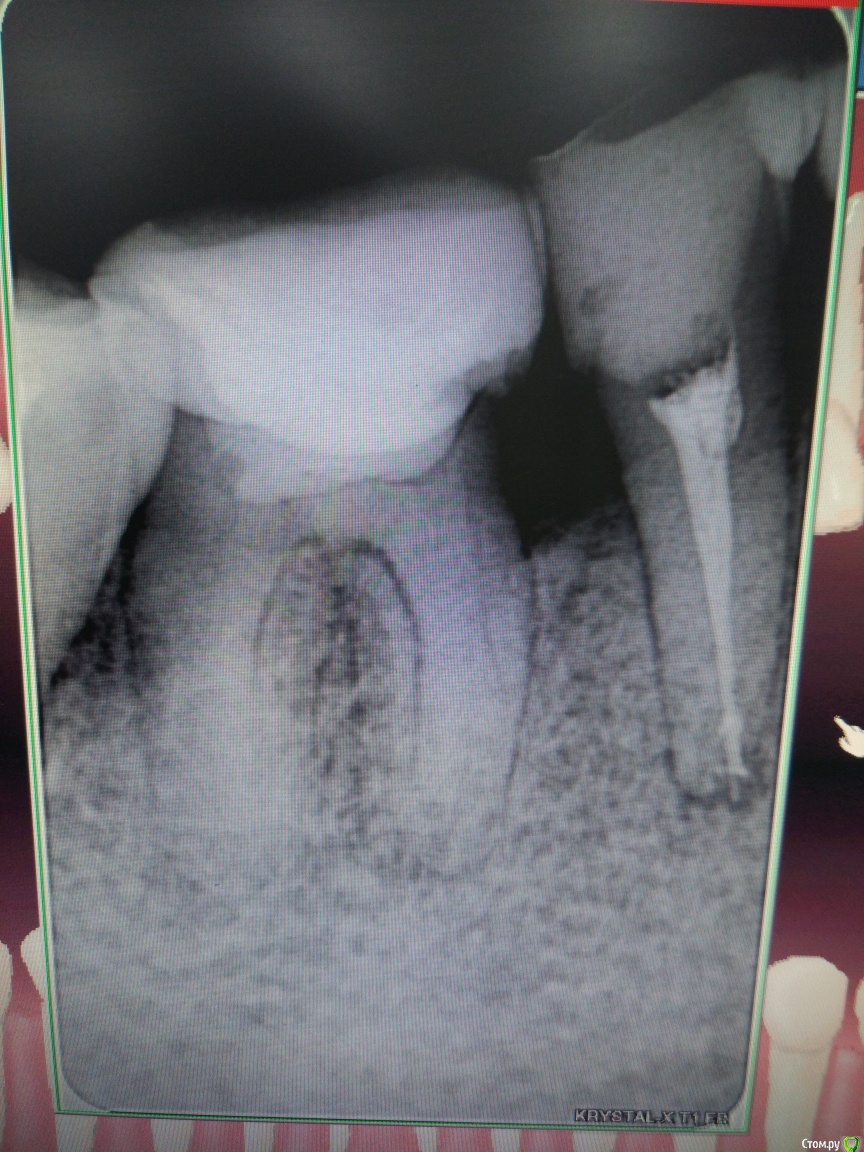

Anna_ni Опубликовано 26 декабря, 2017 Поделиться Опубликовано 26 декабря, 2017 Здравствуйте!Я очень хотела бы получить совет от стоматологов. Заранее спасибо!Дело в том, что нижний зуб справа лет 15 тому назад был лечен резорцин-формалиновым методом.Все это время он не беспокоил. Коронковая часть практически разрушена. Не так давно мой лечащий врач восстановил зуб пломбой до уровня остальных зубов (до этого зуб находился несколько ниже). Через полтора месяца после этого он начал беспокоить. Появилась пульсирующая боль, не постоянная, появляется время от времени. Терапевт дал рекомендацию обратиться за помощью в клинику, где есть микроскоп ( она у нас в городе одна), в которой мне назвали достаточно большую сумму за лечение без гарантии за результат. Теперь меня терзают сомнения стоит ли лечить этот зуб или все-таки вырвать его и установить имплантат? Есть ли смысл в его лечении?Снимок прилагается. Ссылка на комментарий

shishok Опубликовано 26 декабря, 2017 Поделиться Опубликовано 26 декабря, 2017 Имплант более предсказуемый вариант в данной ситуации(убыль костной ткани,отсутствие достаточного объема твердых тканей зуба).ИМХО Ссылка на комментарий